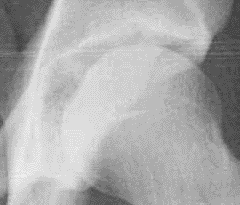

Review Acetabular AP Xray Landmarks